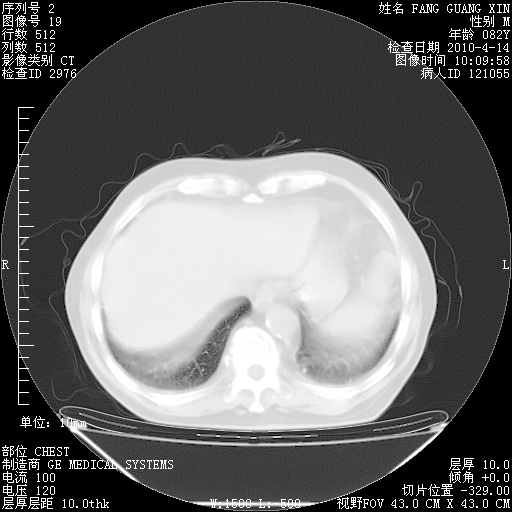

4月14日肺部CT

23.JPG

24.JPG

25.JPG

26.JPG